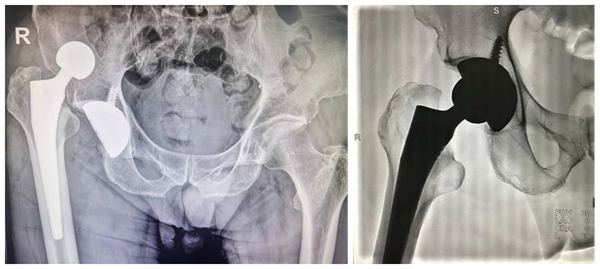

施妙手闭合巧复位,打配合疗效获称赞

2022年1月10日凌晨2点,刚做完人工髋关节手术一月的老邓在家不慎跌倒,顿感右髋剧痛伴活动受限,因老邓所在社区采取疫情封控管理,咨询我院骨二科李浩鹏主任、李锋涛副教授并在其建议下,转运至西安交大二附院大明宫定点救治医院(...